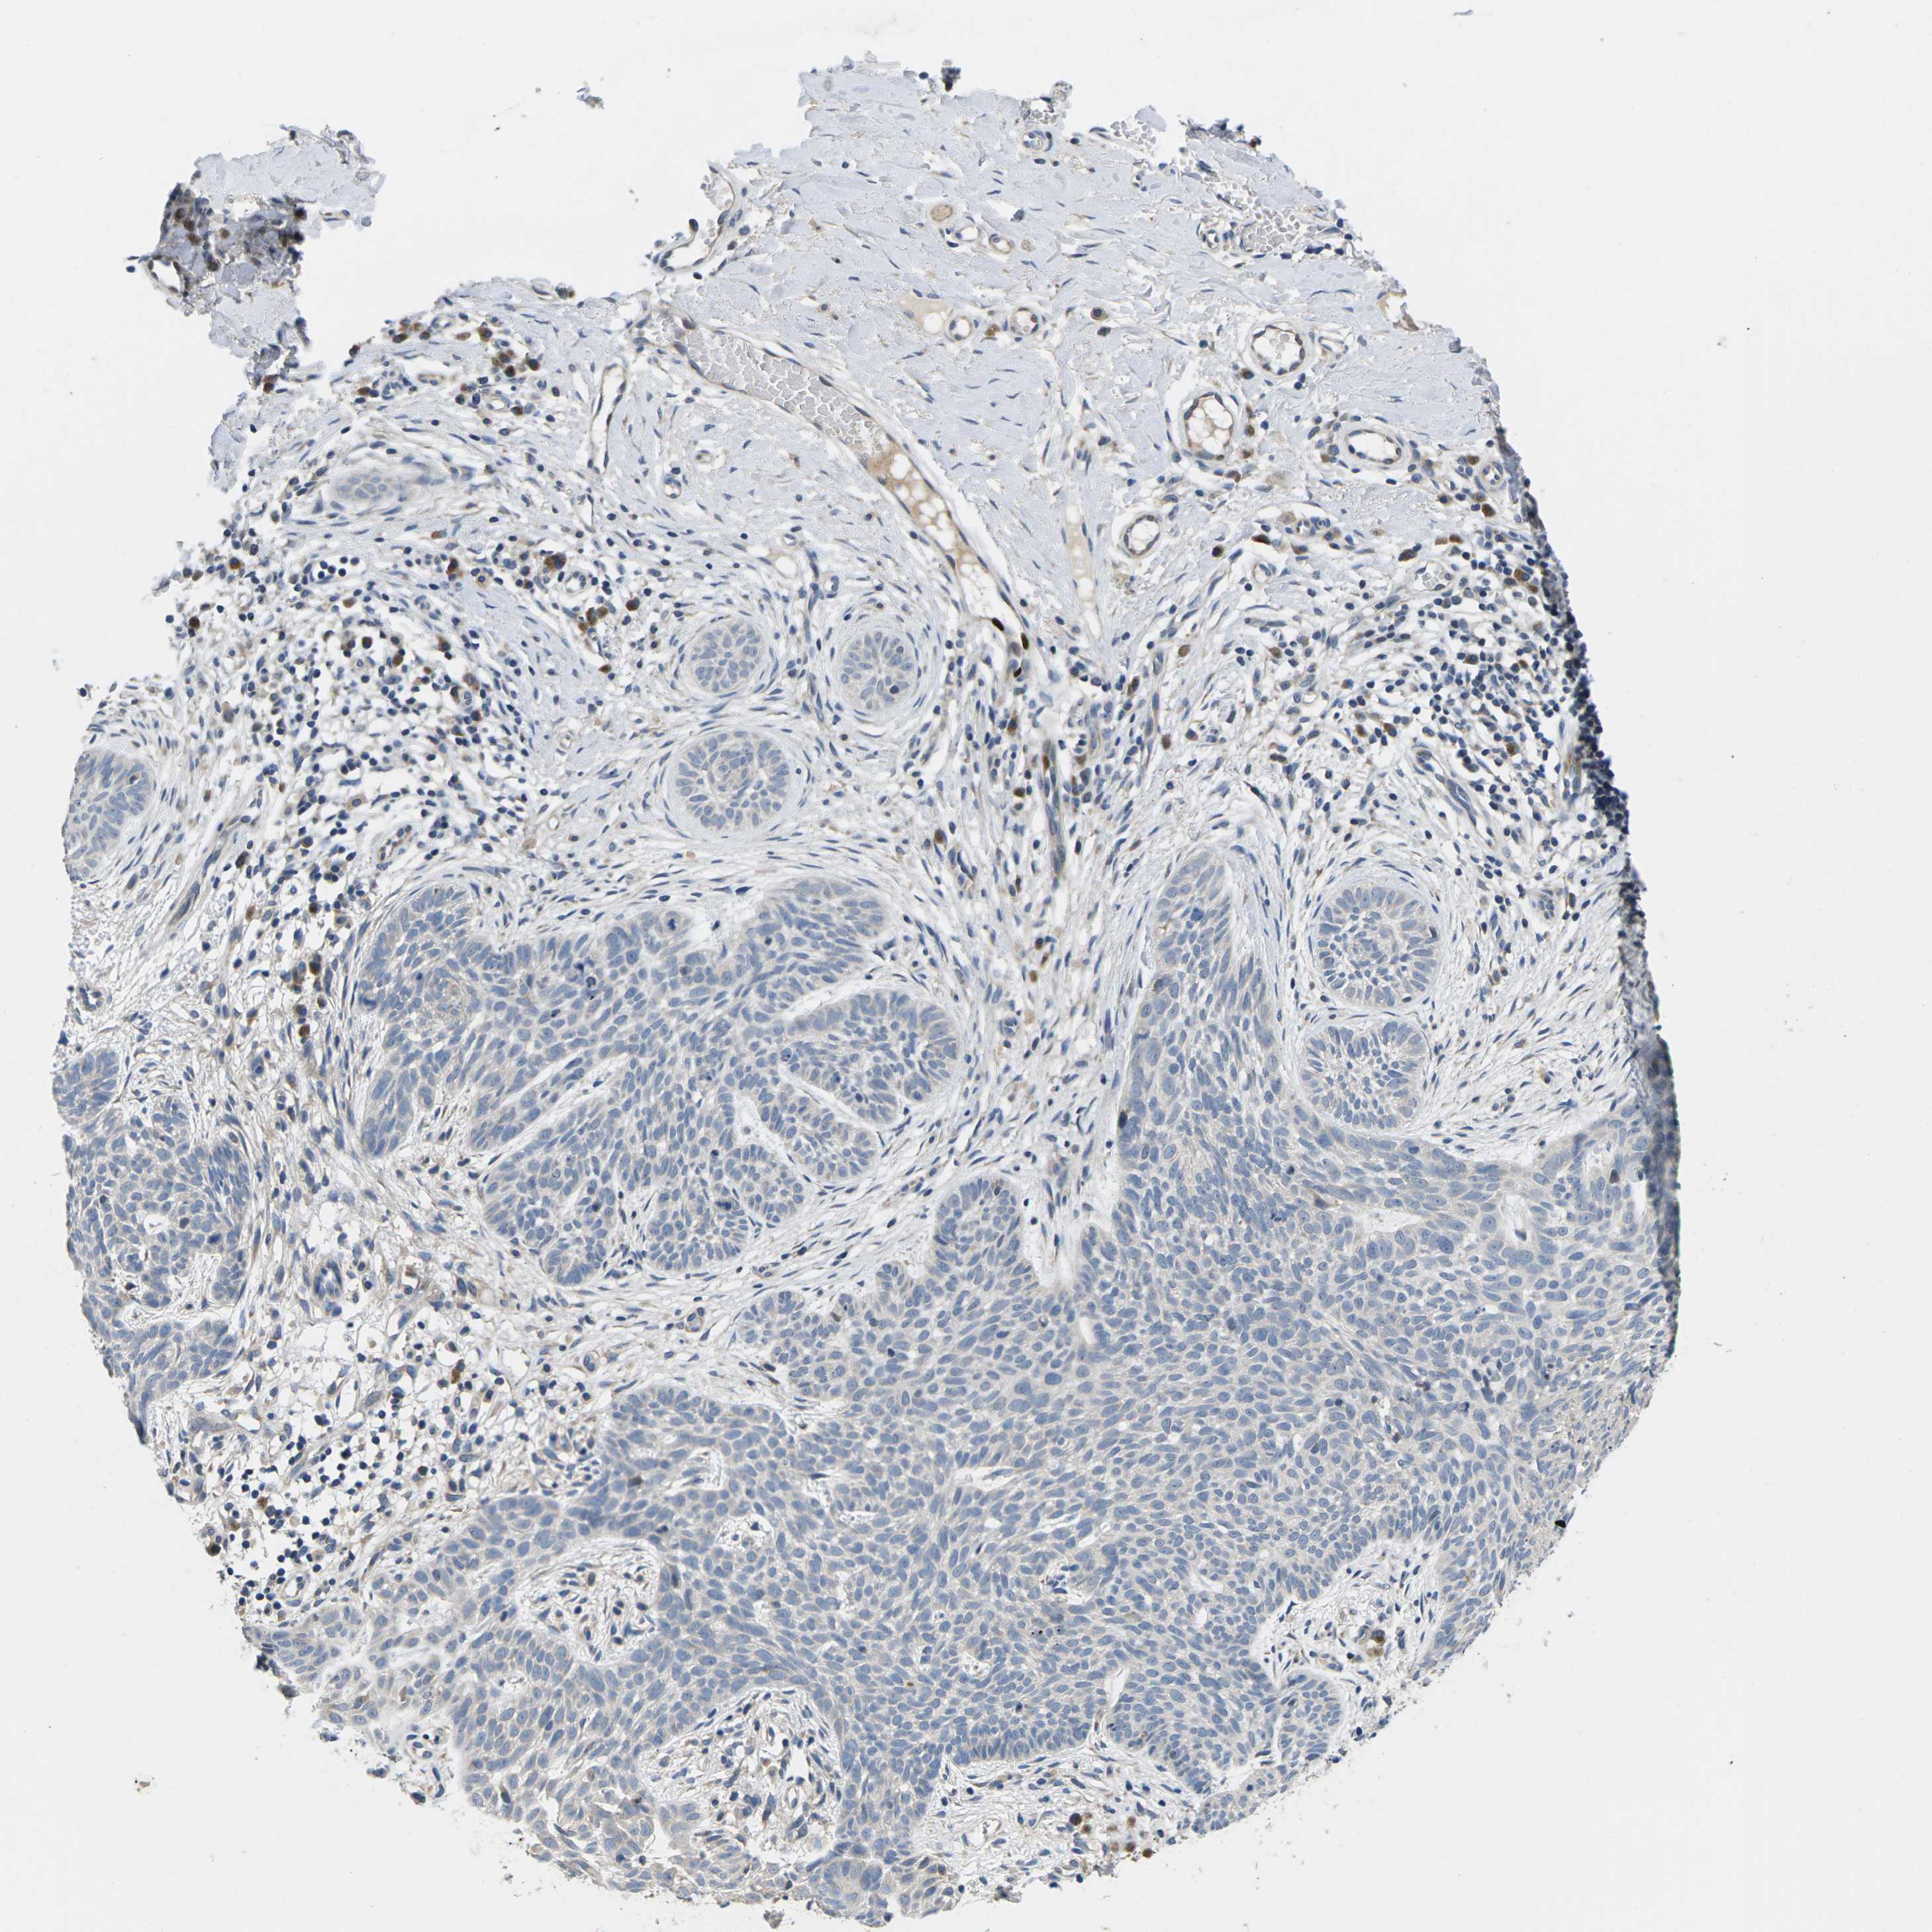

SKIN CANCER - Protein expressioni

A mouse-over function shows sample information and annotation data. Click on an image to view it in a full screen mode. Samples can be filtered based on level of antibody staining by selecting one or several of the following categories: high, medium, low and not detected. The assay and annotation is described here.

Each image is clickable and will lead to virtual microscopy that enables deeper exploration of all samples and also displays staining intensity scores, fraction scores and subcellular localization as well as patient and tissue information for each sample.

Antibody HPA015968

Squamous cell carcinoma, NOS